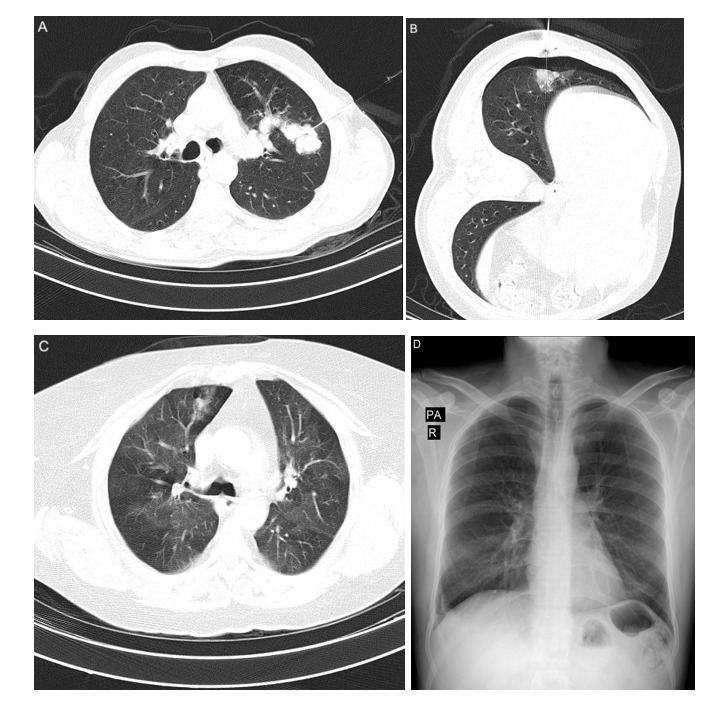

Results: The overall complication rate was 37.9% (95% CI, 27.6%-48.3%), with pneumothorax being the most common, occurring in 26.4% (95% CI, 17.3%-35.6%) of cases, followed by perilesional hemorrhage (17.2%) (95% CI, 10.3%-25.3%), hemoptysis (3.3%), and pleural effusion (1.1%). All pneumothorax cases were identified via immediate post-biopsy CT, and only 1 patient required chest tube insertion. No significant correlations were found between age, sex, presence of emphysema, lesion size, location, and depth, or needle path and the incidence of pneumothorax. However, a significantly higher perilesional hemorrhage incidence was observed for smaller lesion size (26 mm [interquartile range, IQR], 13,40 vs 43 mm [IQR, 24,73]; P = 0.019), deeper lesion (10 mm [IQR, 0.17] vs 0 mm [IQR, 0.10]; P = 0.041), and longer needle path (17 mm [IQR, 9.29] vs 0 mm [IQR, 0.7]; P < 0.001). Furthermore, 47.8% of pneumothorax cases identified on postbiopsy CT showed no signs on follow-up chest X-ray 3 hours later.

Conclusion: TTNB is generally safe, with a manageable complication profile. Early detection and appropriate follow-up are crucial, particularly for pneumothorax, which often resolves spontaneously. The findings underscore the importance of considering lesion characteristics to minimize complications during biopsy procedures.